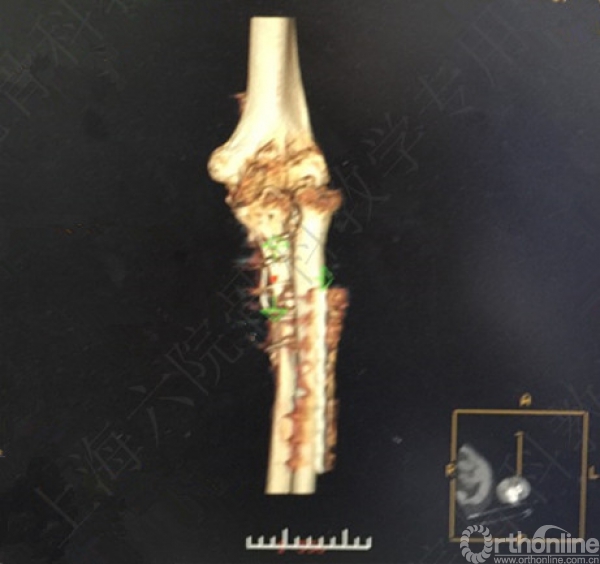

X线及CT示:左尺桡骨骨不连,尺骨力线差,成角,桡骨头脱位,创伤性关节炎。

患者择期行左尺桡骨取原内固定+切开复位内固定术+髂骨异体骨植骨+桡骨头切除术。